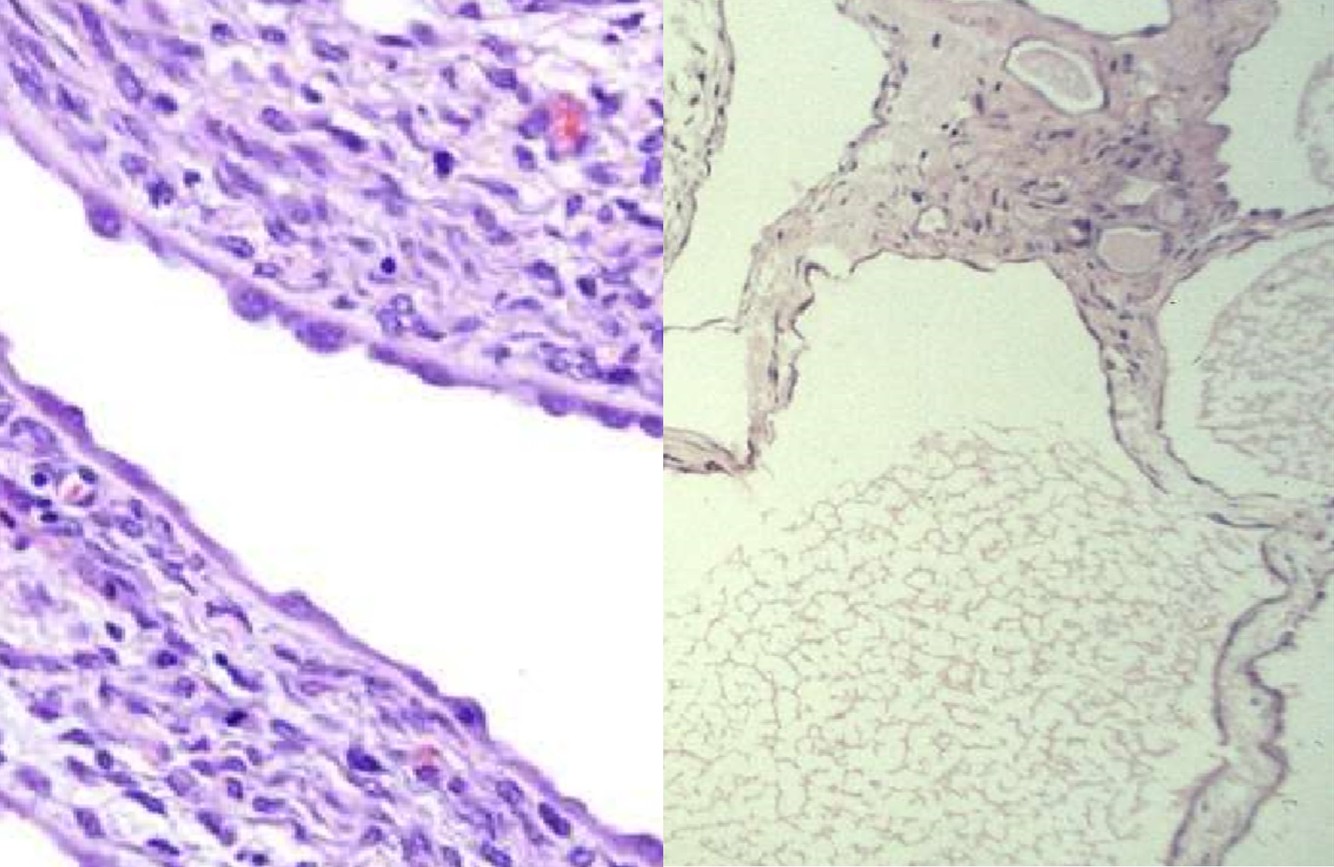

CYSTIC NEPHROMA

- Presents as a multilocular renal cyst

- Bimodal in age distribution: children less than 4 years of age, young women

- Excellent prognosis

MULTILOCULAR CYSTIC RCC

- Presents as a multilocular renal cyst

- Excellent prognosis; classified by the WHO as a neoplasm of low-malignant potential